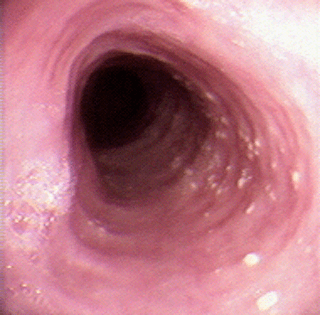

Endoscopic view of the esophagus in a 36-year-old male with dysphagia. Dx?

Eosinophilic Esophagitis

(whitish papules are also visible representing eosinophilic abscesses)